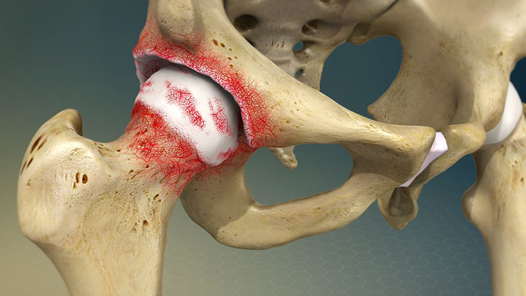

1.2. Qué sucede en la artrosis de cadera?

Con el paso del tiempo (o en algunos casos, por causas específicas), el cartílago de la cadera comienza a degenerarse o desgastarse. Esto provoca:

- Pérdida de la superficie lisa del cartílago, haciendo que los huesos rocen directamente entre sí.

- Inflamación de la articulación, con engrosamiento de la cápsula sinovial.

- Formación de osteofitos o "picos de hueso" en los bordes articulares.

- Disminución del espacio articular observable en radiografías.

- Cambios en la forma o alineación de la articulación.

Este proceso produce dolor progresivo, pérdida de movimiento y, en etapas avanzadas, deformidad e incapacidad funcional.